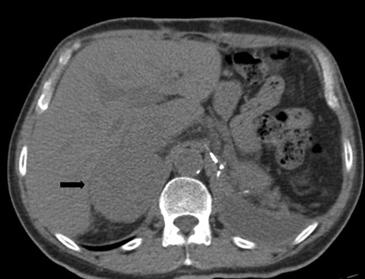

En la TC no contrastada las glándulas suprarrenales normales son homogéneas y simétricas, con una densidad muy similar a la del parénquima renal adyacente (Figura 1 a). Con un medio de contraste ev la glándula suprarrenal se opacifica en forma homogénea, similar al hígado o al bazo (Figura 1 b). Si la cantidad de tejido adiposo retroperitoneal es abundante las glándulas suprarrenales pueden aparecer enteramente rodeadas por grasa y su delimitación es más fácil (Figura 2 a); lo inverso ocurre en pacientes muy delgados con escasa grasa retroperitoneal (Figura 2 b). En RM, en secuencias ponderadas en T1 y T2 convencionales tienen una intensidad de señal homogénea, hipointensa respecto de la grasa adyacente e iso o hipointensa con respecto del parénquima hepático (Figura 3 a y b). En los cortes coronales se aprecia mejor la forma y la posición de las glándulas suprarrenales (Figura 3 c).

Figura 1. Glándula suprarrenal normal en tomografía computada. Cortes axiales de tomografía computada, donde se identifica la morfología normal de la glándula suprarrenal derecha (flecha) en fase no contrastada (a), y tras el uso de medio de contraste endovenoso (b).